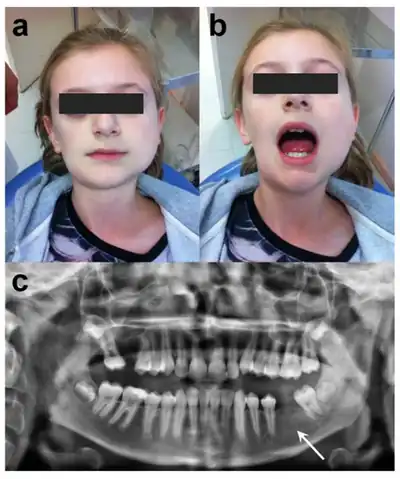

| a) Frontal view b) limited mouth opening of 25 mm, c) panoramic radiograph | |

- Trismus (difficulty opening the mouth), which may be present in some cases and is caused by edema in the muscles.